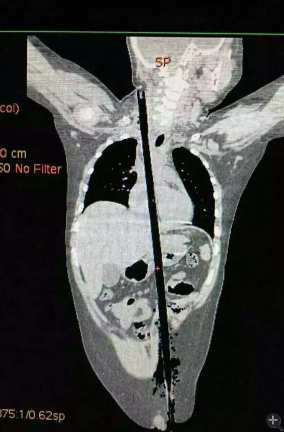

據(jù)相關(guān)知情人介紹,受傷男童24日晚在家中與小朋友一塊兒在墻頭上玩耍時,一不小心從高墻上跌落到了鄰家花圃中,讓人觸目驚心的是,該男童正好跌到了花圃中的一支長約63厘米,直徑約1.5厘米的竹棍上,竹棍自孩子的左側(cè)大腿根部直接插入腹腔并入胸腔直至右側(cè)頸部。

市兒童醫(yī)院組織專家團隊對孩子的病情進行檢查、評估后發(fā)現(xiàn),竹棍由患兒左側(cè)大腿根部插入,經(jīng)腹腔穿透胃、肝臟、膈肌入胸腔,并穿透患兒心臟,經(jīng)胸腔入頸部,此刻不能拔除竹棍,因為去除竹棍會導致心臟、肝臟破裂大出血導致休克,危及性命。

由于竹棍自心臟的右心房膈面穿入心臟,并由右房近左房頂處穿出心臟,經(jīng)右胸頂刺入右頸部,右心房破口處緊鄰右冠狀動脈,幸運的是胸腔內(nèi)大血管無損傷,在體外循環(huán)輔助下,醫(yī)護團隊異物穿出處鋸斷異物,將插入心臟內(nèi)的竹棍截斷拔除,修補心臟破損處,向上繼續(xù)尋找周圍組織的游離異物,見異物緊臨頸部大血管,經(jīng)精細手術(shù),終于抽出了異物。整個手術(shù)時間花了十多個小時。